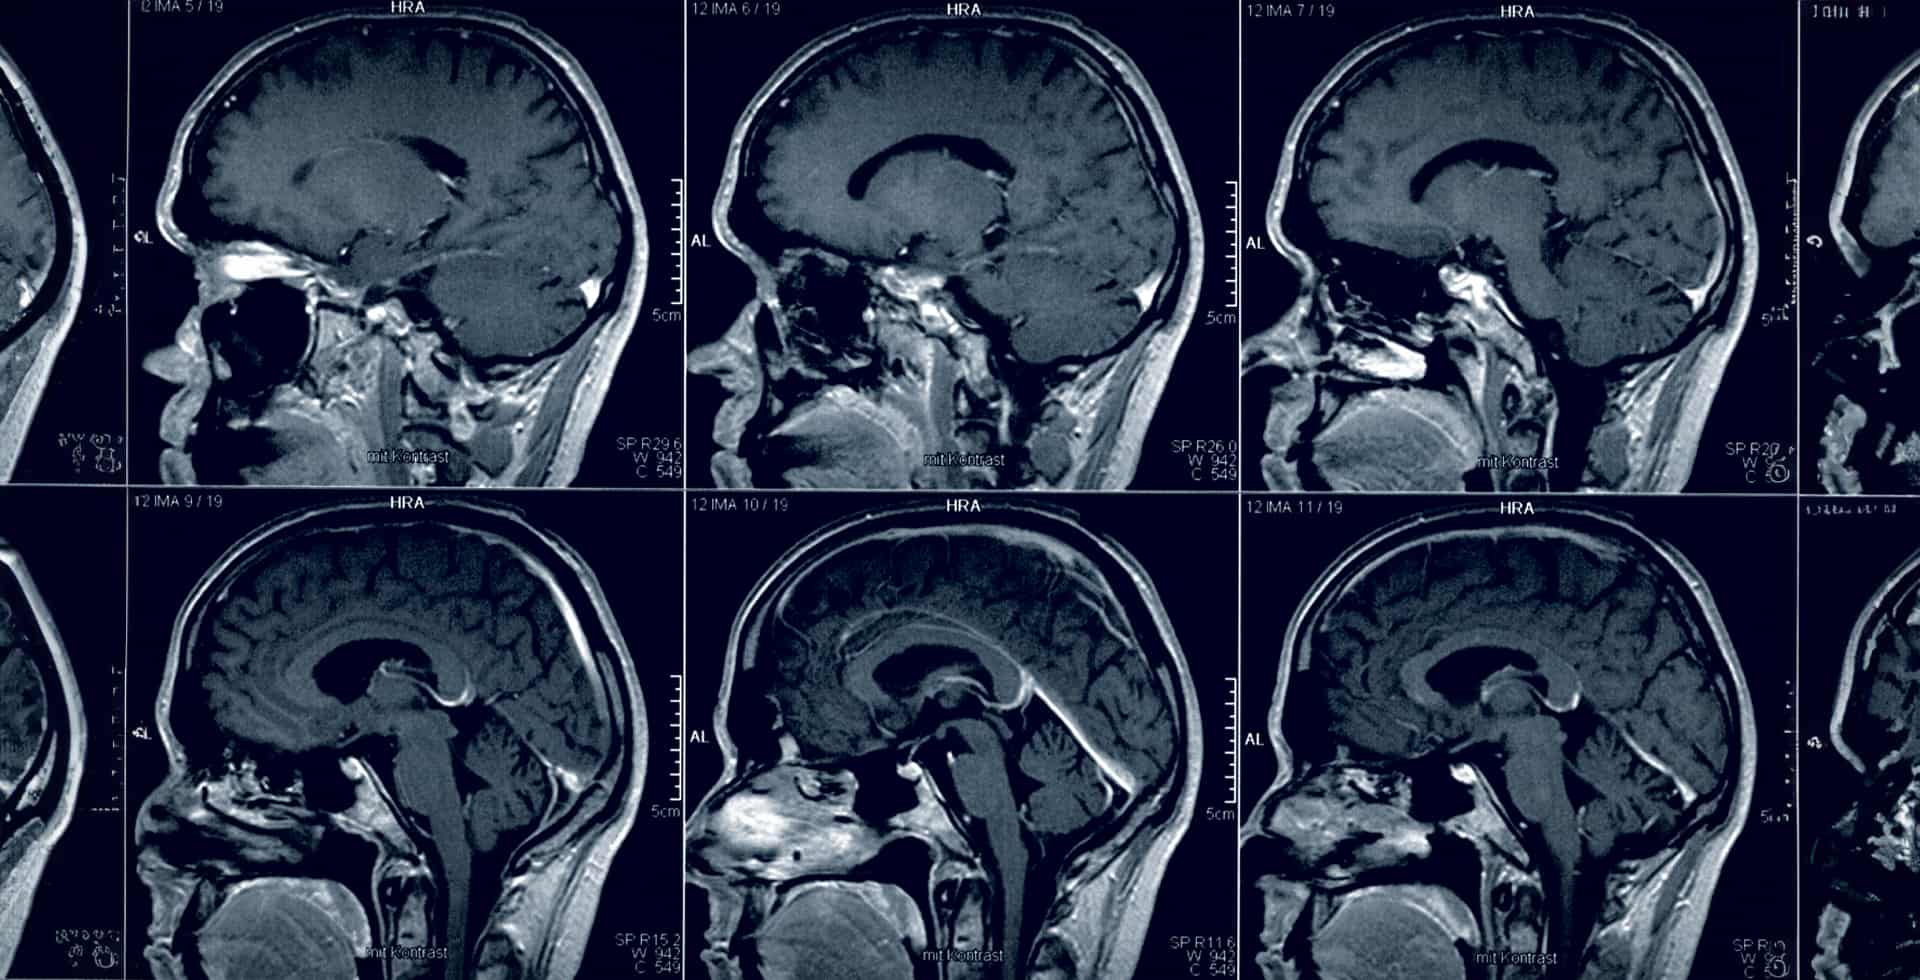

Magnetisk resonanstomografi (MRI) av en hjärna.

Sex miljoner till framtidens hjärnforskare

Hjärnfonden delar ut sex miljoner kronor i form av postdoktorala stipendier till tio forskare i början av sina akademiska karriärer.